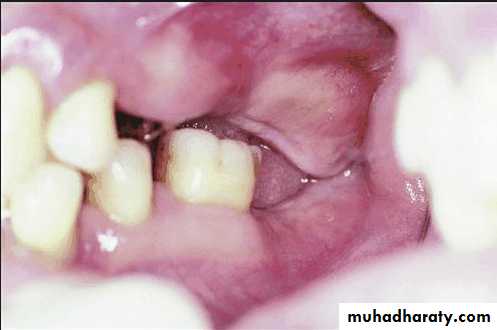

Evaluation of soft tissue abnormalities

Various tissue conditions can present problems in the design and construction of removable partial denture.Labial and lingual frena as well as un supported and hyper mobile gingiva should be evaluated to determine whether surgical correction will improve the prognosis of the treatment

Evaluation of oral mucosa

Pathologic changes:Any ulceration, swelling , or color change that might indicate malignant or pre malignant changes should be recognized and evaluated through biopsy or referral.

Palatal papillary hyperplasia:

Caused by inflammatory response in the sub mucosa, consists of numerous papillary growths.Food debris, fungi, bacteria collect in the crevices and may give rise to secondary infection.

If the patient will not be able to keep the lesion adequately clean, it should be removed.